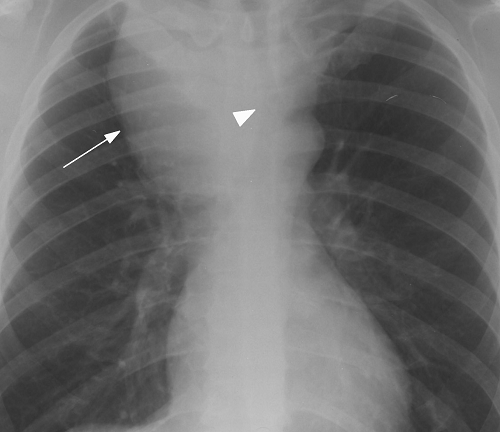

Imaging Tests

The detailed view of the paratracheal region is observed through different imaging tests like, MRIs, X-rays, and CT scans.